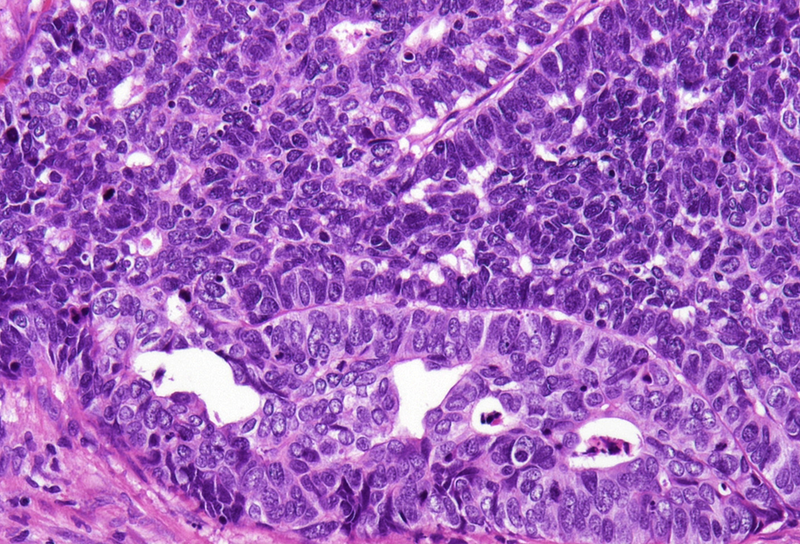

Histological examination showed a solid neoplasm with a predominantly nodular to lobulated growth pattern, frequently exhibiting peripheral palisading and central areas of comedonecrosis, located in the anal transitional zone (Panel A). The neoplastic cells were small to medium-sized, with scant cytoplasm, hyperchromatic nuclei, and inconspicuous nucleoli (Panel B). Glandular differentiation was minimal to absent (Panel C). The lesion showed focal connection with the overlying surface epithelium, which exhibited areas of papillary architecture with downward extension of neoplastic nests into the underlying stroma (Panel D).  The overall morphological features were consistent with a poorly differentiated carcinoma, not clearly indicating glandular and/or squamous differentiation.